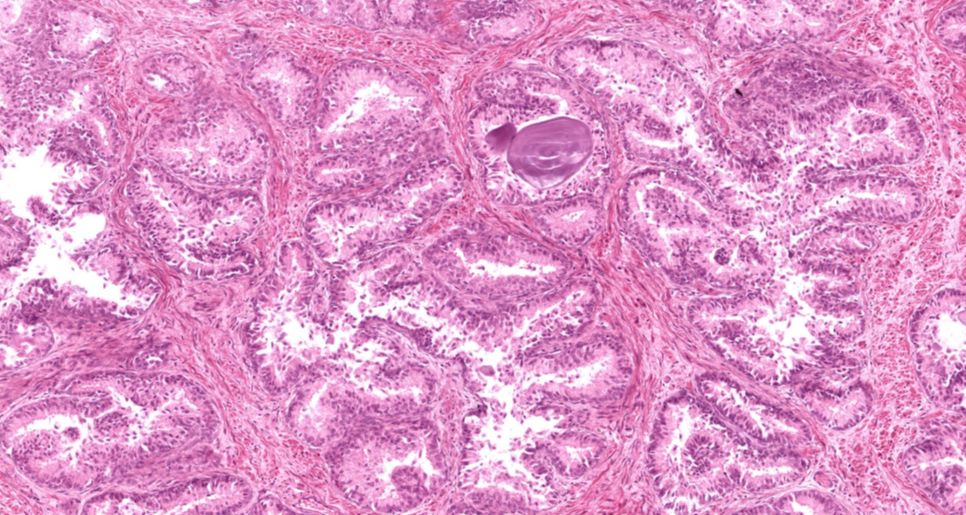

Próstata

Concreções prostéticas